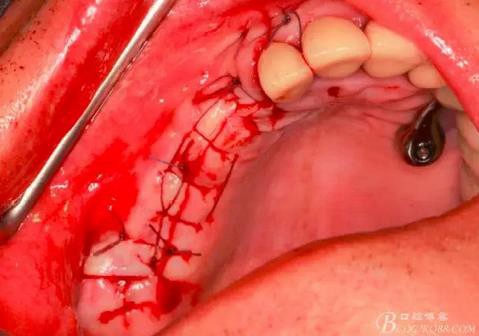

習(xí)慣性的在竇膜下貼服一張膜保護。

生物膜平整地貼附在竇膜上。

同種異體骨松質(zhì)骨與Bio-oss骨粉混合。

用骨粉充填器植入骨粉。

14,15牙位植入兩顆植體,6,7牙位骨高度嚴(yán)重不足,且骨密度低,無法給植體提供良好的初期穩(wěn)定性,需二期植入。13牙位骨寬度不足,沒有植骨、植植體,修復(fù)時用后面4顆連冠加一顆3的游離臂是沒有問題的。當(dāng)然這里我們不去討論這個方法的合理性,我們今天的話題是改良式外提升技術(shù)的應(yīng)用。